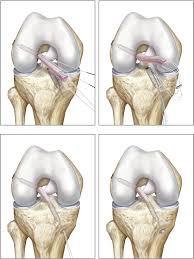

και η τοποθέτηση αυτού γίνεται μέσα από την άρθρωση του γόνατος όπου με ειδικά εργαλεία δημιουργούνται τούνελ στο μηρό και στη κνήμη από μέσα από την άρθρωση προς τα έξω.

Άρα τα τούνελ είναι πλέον μικρότερα σε μήκος από τις σύνηθες τεχνικές με αποτέλεσμα να μην πειράζουμε το έξω τμήμα του οστού (corticalis), η απώλεια οστού είναι αρκετά λιγότερη και τα μαλακά μόρια προφυλάσσονται στο μέγιστο.

Η καθήλωση του τένοντα γίνεται και στο μηρό και στη κνήμη με μκρά φύλλα τιτανίου μήκους ενός εκατοστού και πάχους ελαχίστων χιλιοστών που βρίσκονται εκτός οστού. Έτσι μέσα στο οστό δεν υπάρχει ξένο σώμα εκτός από τα ράμματα.